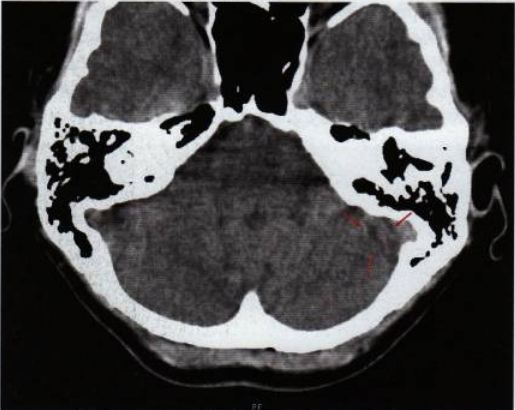

- Imagen 08: La TAC original del 10.6.2009: Las flechas rojas indican un foco hameriano en las glándulas mamarias del seno izquierdo. El semicírculo interno e izquierdo de la abertura todavía está activo y en conflicto. El lado externo derecho ya no muestra un borde afilado, sino manchas oscuras (= retención de líquidos-edema), una indicación del inicio de la curación. Hallazgos: ¡El conflicto todavía está medio activo y medio resuelto!